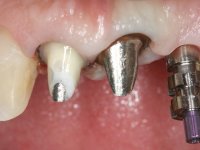

Endodontic treatments were performed and a metalic non screwed intra radicular post was placed on tooth 1.1. An alginate impression was made for laboratory confection of a reinforced acrylic provisional bridge, with teeth 1.1 and 2.2 as abutments and 2.2 as a pontic. After preparation of tooth 1.1 and root preparation of 2.1, the bridge was relined in mouth with self-polymerizable acrylic using a metal post for further retaining the prepared root canal on 2.1. Tooth 2.2 was cut at the gingival level to function as support. In the same session, the impression of the root canal of the 2.1 was made for the laboratory confection of a cast post and core. A double mixture technique with plastic tutor was used after previous canal vaseline with endodontic file and cotton. The provisional bridge was provisionally cemented and the cast post and core was made in the laboratory. Cast post and core cementation was made with resin-reinforced glass ionomer cement and the provisional bridge had to be readjusted to the new situation by removing the post at the site of 2.1. After careful surgical planning, a dental implant was placed, simultaneously with extraction of the root of tooth 2.2. The provisional bridge was placed by resting on the healing screw placed in the implant. The respected osteointegration period was 12 weeks, during which the provisional bridge was relined twice. After complete maturation of hard and soft tissues, definitive impressions were made. The gingival retraction technique was applied with an impregnated retraction cord and impression was performed using double mixture, open tray impression technique. A custom precious metal abutment implant was prepared in the lab, along with 3 metal caps to be used as infrastructures for the metal ceramic crowns. Particular care was taken in the confection of the cervical finishing line of the implant abutment, in order to follow the soft tissues emergence profile. Proof of infrastructures was done in the mouth being evaluated clinically and imagiologically. Collection of color information was done by the ceramist at the office. Ceramic was applied in the laboratory and the finished work was placed in the mouth after approval by the patient. Definitive cementation was made with resin-reinforced glass ionomer cement, and the first crown to be cemented was that of the implant, to facilitate removal of the excess.